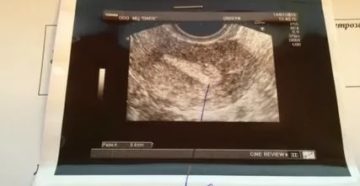

Беременность после кесарева: нужно ли смотреть толщину шва? После родов путем кесарева сечения начинается процесс…